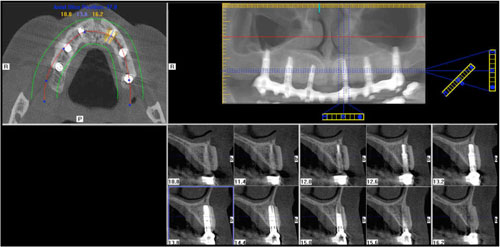

Επίσης, πλέον μία πολύ συχνή επέμβαση είναι η τοποθέτηση οστικού μοσχεύματος στα ιγμόρια άντρα για δημιουργία οστικού όγκου, με σκοπό την τοποθέτηση οδοντικών εμφυτευμάτων στην άνω γνάθο.

Αποτελεί και αυτή επέμβαση ρουτίνας για τους Στοματικούς και Γναθοπροσωπικούς Χειριουργούς, με αποτέλεσμα που αγγίζει σχεδόν πάντα το άριστο. Και εδώ το πιό συχνό αίτιο αποτυχίας, είναι το ίδιο όπως αναφέρθηκε πρωτύτερα για τους φρονιμίτες. Είναι πλέον γνωστό σε όλους ότι τα οδοντικά εμφυτεύματα συμβάλλουν στην αποκατάσταση της λειτουργίας της μάσησης, της κατάλληλης σύγκλισης και της διατήρησης  του οδοντικού φραγμο